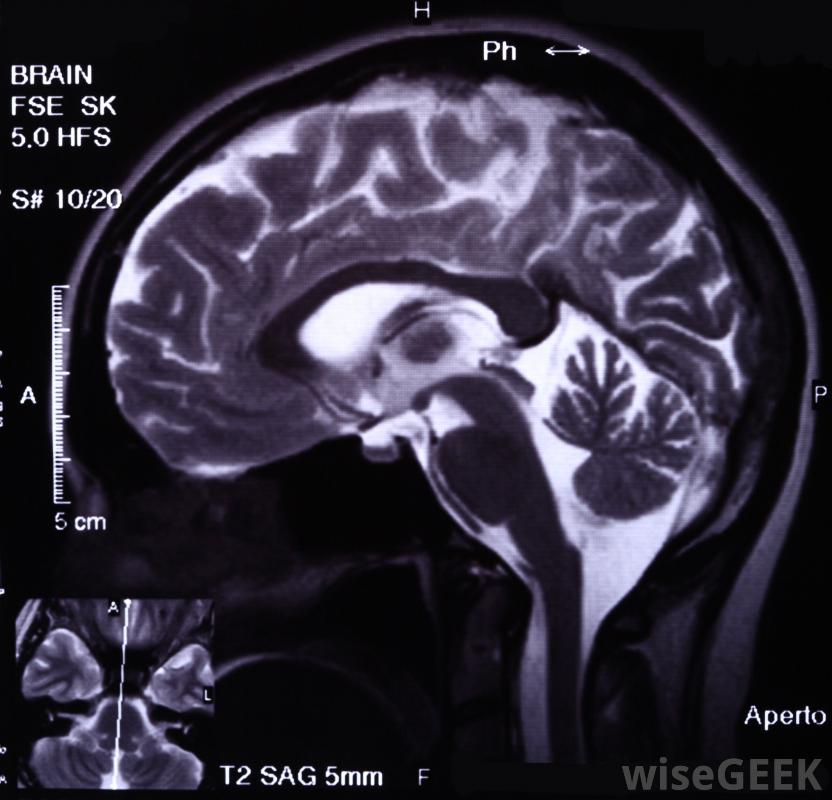

SPECT扫描可用于追踪大脑中的血流伽玛照相机本身不会发出任何辐射,但是,它可以在潜在疾病发生的部位,从体内的放射性药物中获取辐射。这种相机可以位于检查台的上方或下方,有时也可以在一台圆形扫描机内找到。一旦病人被插入机器中,它就能够旋转并成像身体。通过成像在细胞水平上,核医学相机能够在疾病和疾病有机会传播和显示组织和身体的外部体征之前检测到疾病和疾病,计算机从摄像机下载信息并协助创建图像核医学相机可用于检测心脏病。单光子发射计算机断层扫描是另一种成像机器,它允许医生拍摄描述流向心脏的血流的图像器官和身体组织。给病人一种伽马射线发射示踪物质,扫描仪采集身体各部分的图像,并将其发送到计算机,计算机最终将横截面分割成3D图像。SPECT扫描通常仅限于血液流经静脉的成像区域。其中一种SPECT扫描的主要任务是绘制和成像流经大脑血管的血流图。

PET扫描使用放射性示踪剂来突出显示身体可能有异常生长的部位另一种核医学相机是PET扫描。这种扫描通常用于检查癌症和心脏病发作的影响。它还可以成像大脑中的任何异常。与其他程序一样,给病人注射示踪剂,让病人躺在一张薄薄的桌子上,这张桌子从机器中间的一个椭圆形的孔滑过。PET扫描仪有许多探测环,能够对示踪物质在病人体内的放射物进行成像